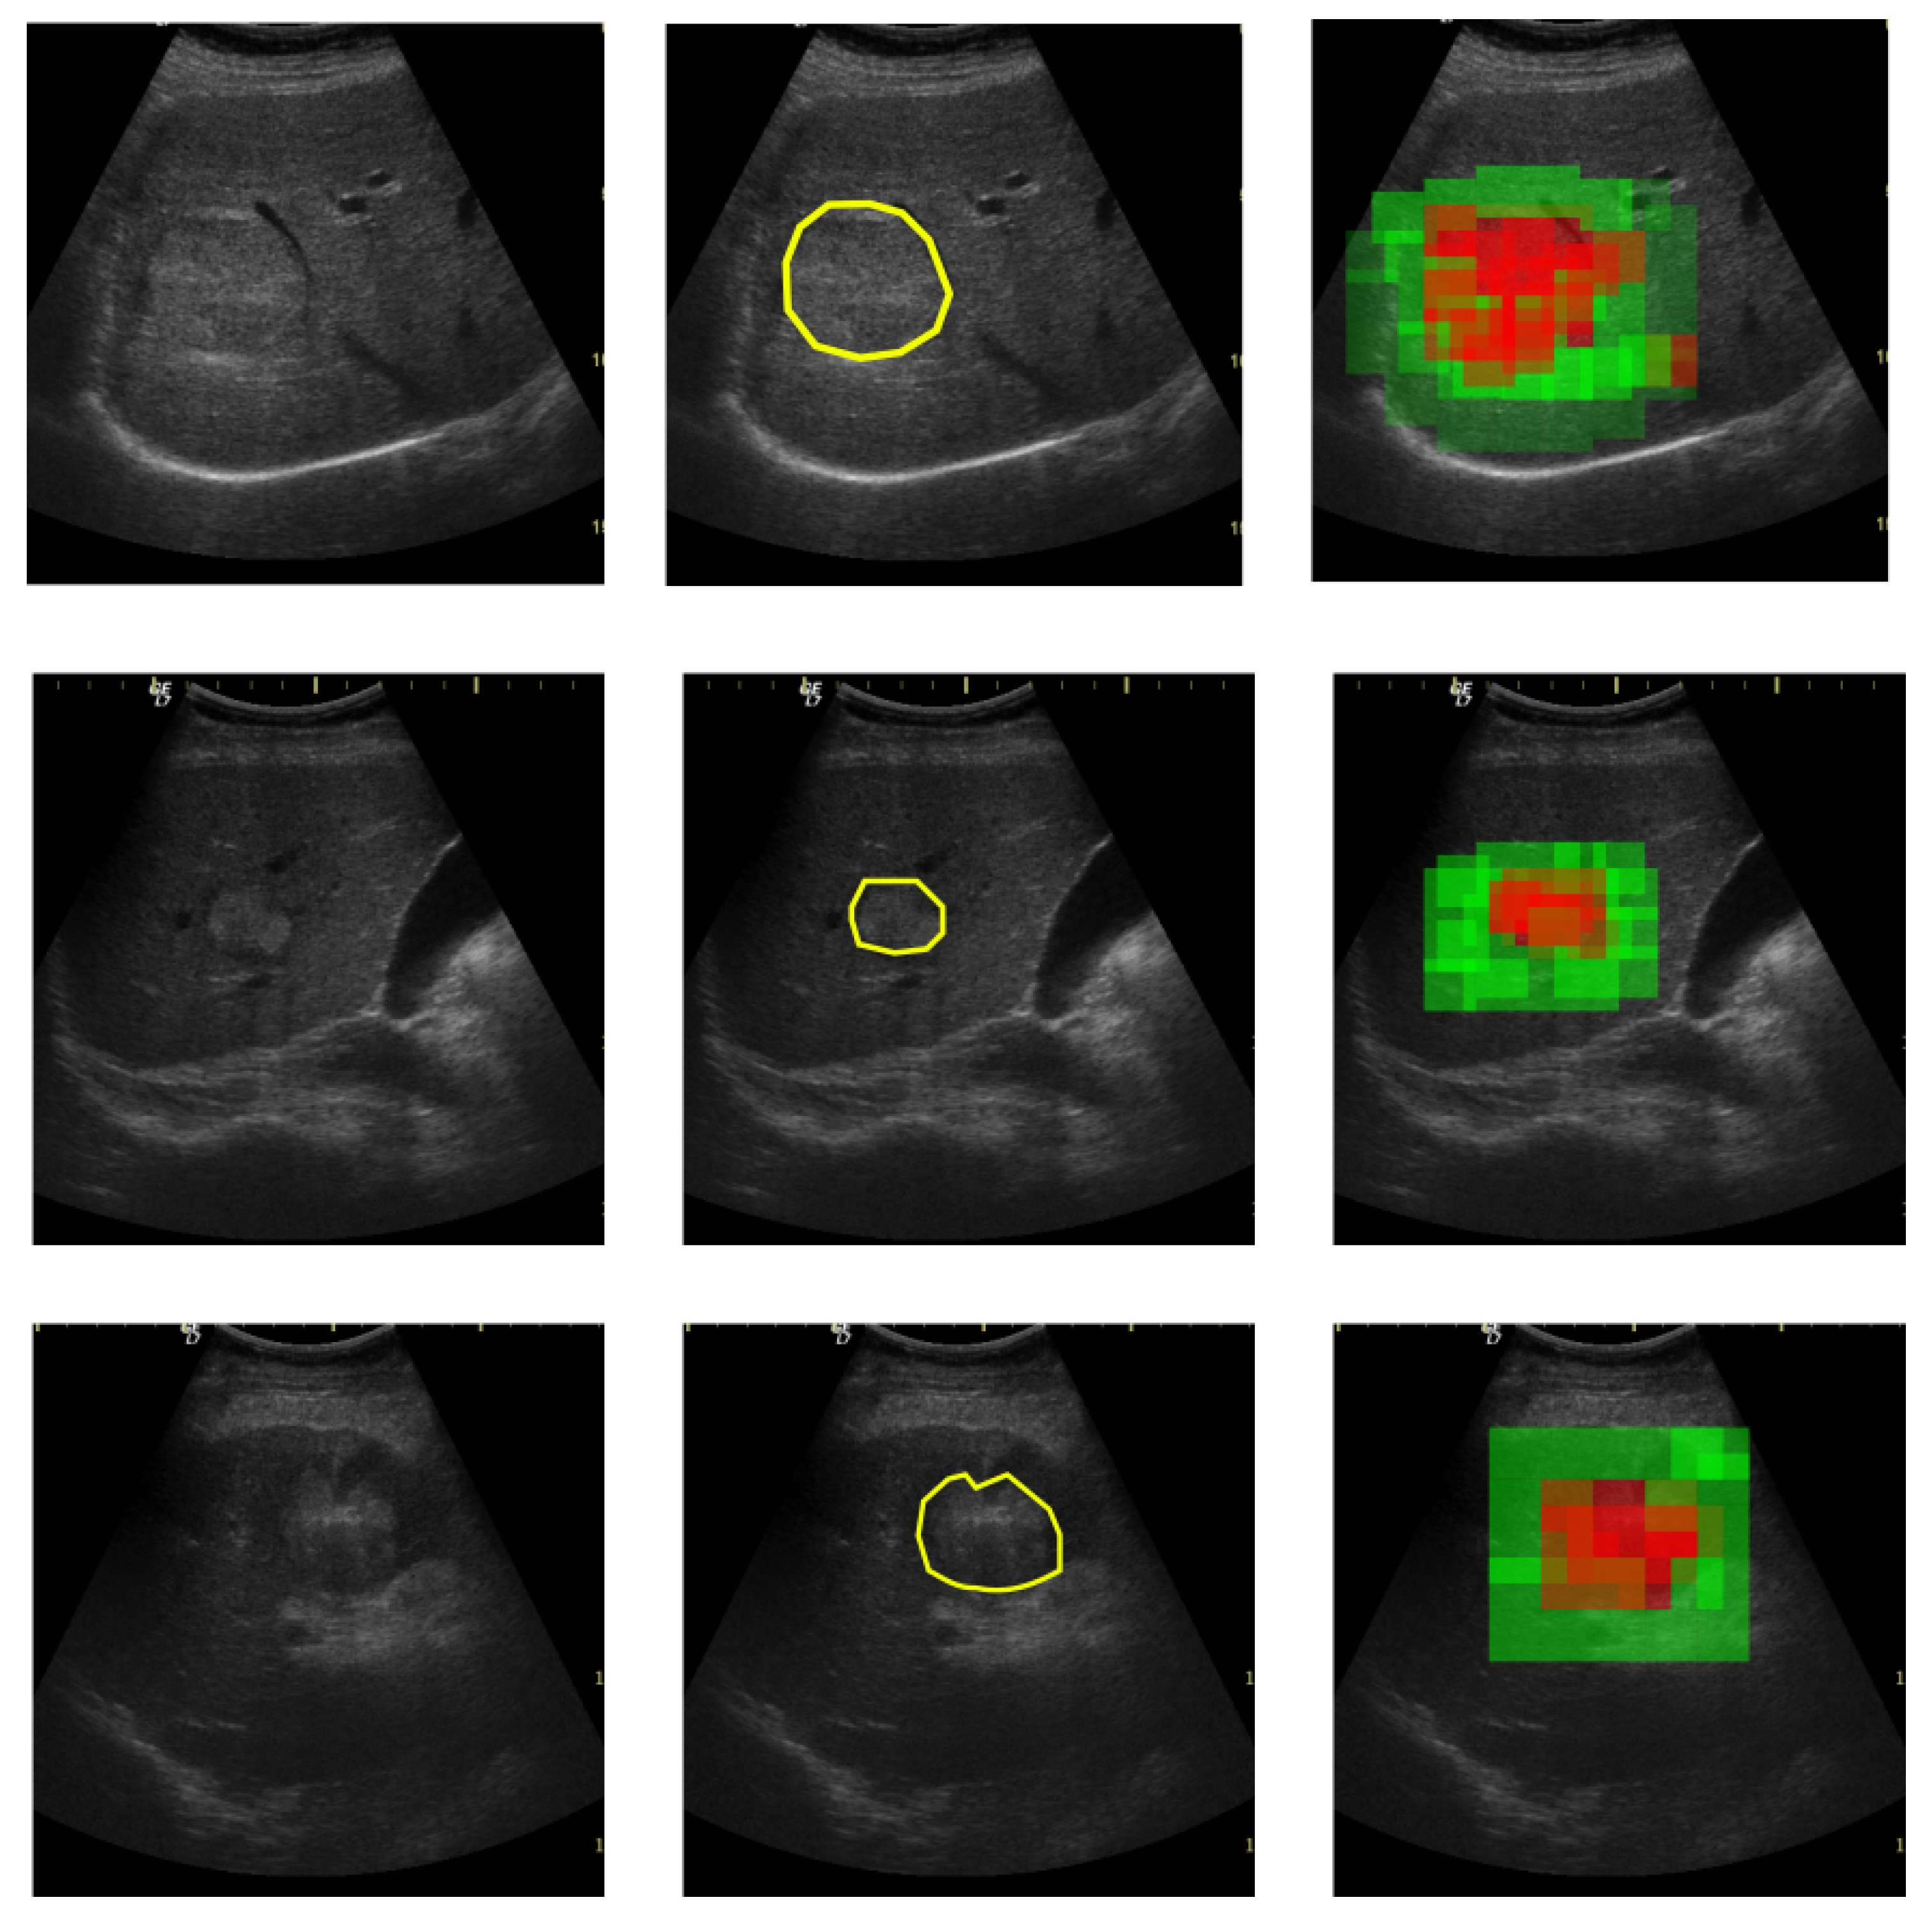

On a large scale, in the context of a medical diagnosis framework, the proposed model can be used for providing a visual trigger for the medical specialist. As depicted in Figure 15, being given an input ultrasound image the medical specialist could select the interest region (marked with yellow) and the proposed method provides a confidence map for that region and its surroundings. Thus, in Figure 15 a high probability of containing a HCC patch is depicted with red and a high probability of PAR is depicted with green.

Figure 15. Input image (left), ground truth with HCC area enclosed in yellow polygon (middle), predicted confidence map in which HCC likelihood of a patch is marked in red and the PAR high confidence is marked in green.